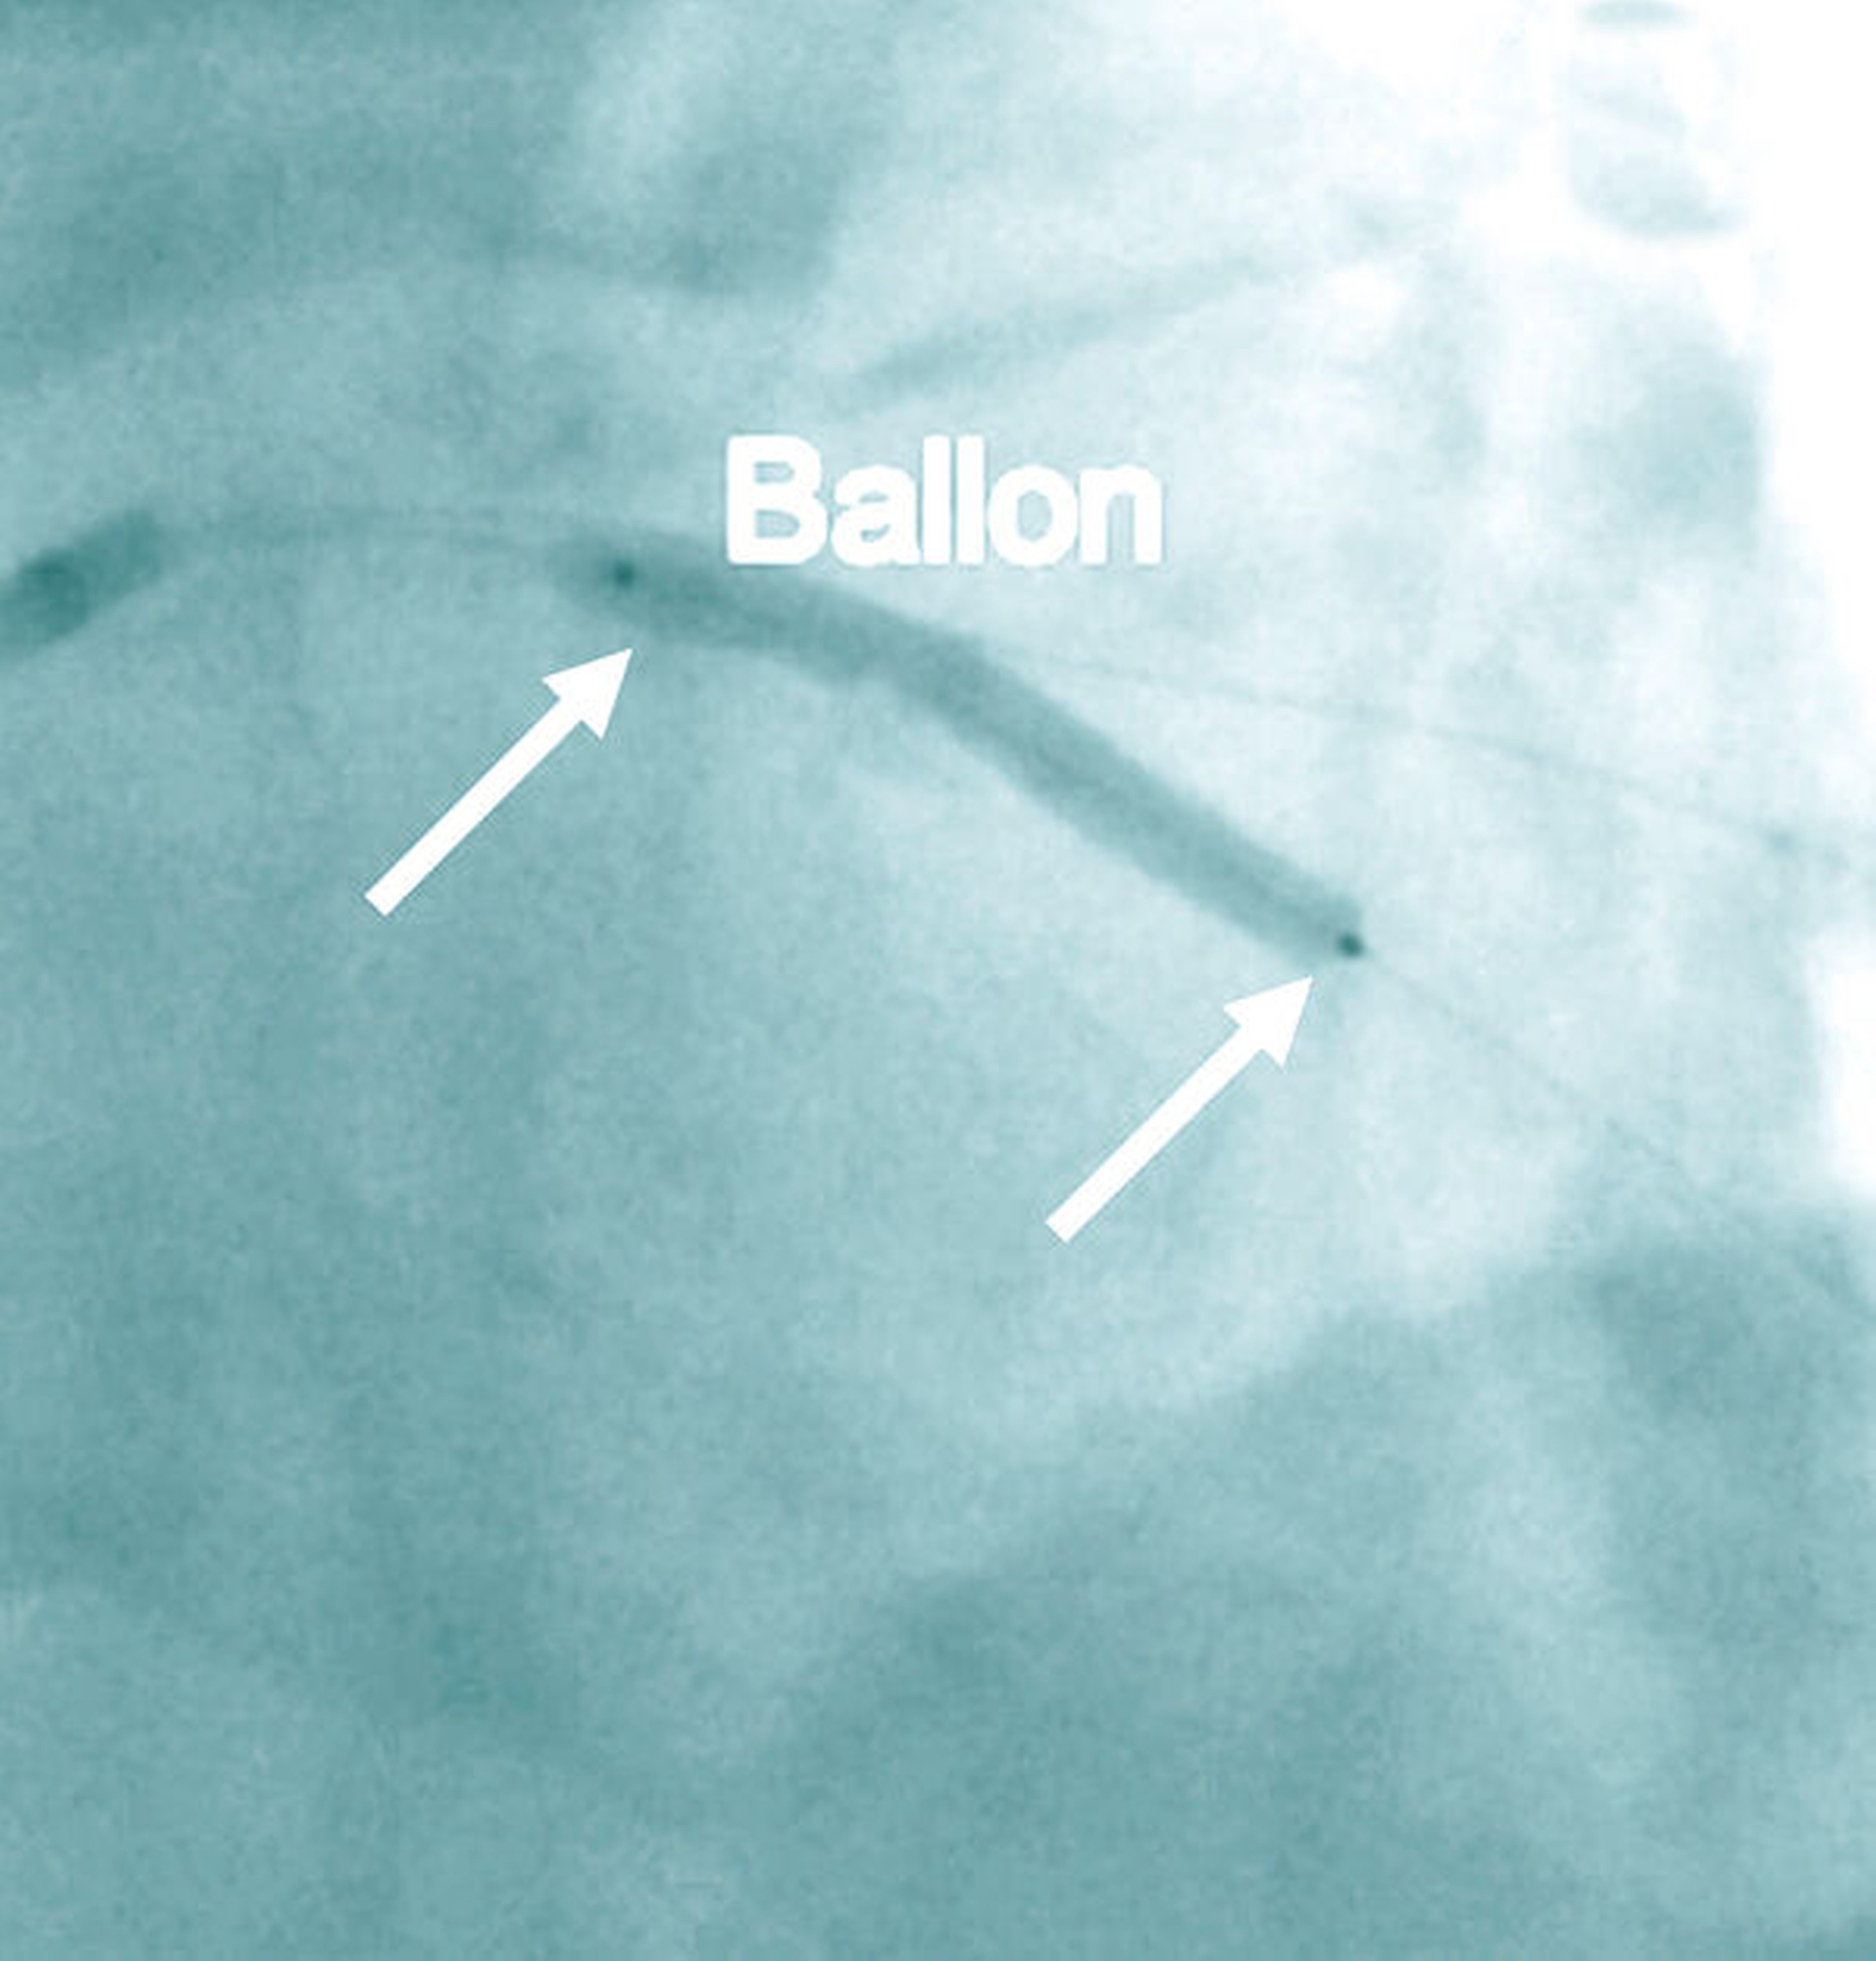

Die KHK ist gekennzeichnet durch arteriosklerotische Veränderungen der Herzkranzgefäße (Abbildung 1a). Die Folge kann eine verminderte Durchblutung und dadurch bedingte Schädigung der Herzmuskulatur sein. Klinische Korrelate für die gestörte Koronardurchblutung sind die Angina pectoris (Brustenge) und Herzrhythmusstörungen bis hin zum plötzlichen Herztod. Ein Herzinfarkt mit nachfolgender Herzinsuffizienz stellt eine bedeutsame Komplikation der KHK dar. Als Therapie kommen bei der Erkrankung der kleineren Gefäße Medikamente (Nitrate, Betarezeptorenblocker, Calcium-Kanal-Blocker) und bei Beteiligung der großen Koronargefäße bevorzugt die Dilatation/Stentversorgung im Rahmen einer interventionellen Therapie oder einer Operation (aortokoronare Bypass-Versorgung) in Betracht (Abbildungen 1b und 1c).